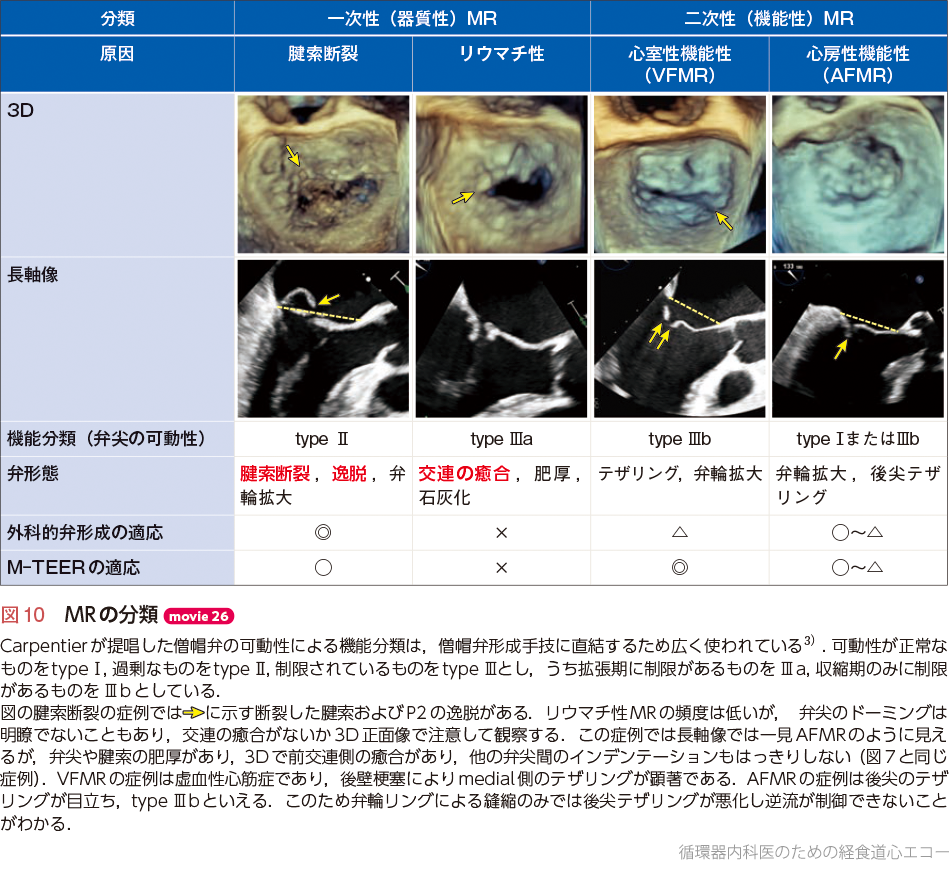

3D心エコー:どうやって使えば手術に役立てられるか? 解剖学的。循環器内科医のための経食道心エコー〜基本的な手技から術中・術。figure4.image1.png。ご覧いただきありがとうございます。「経食道心エコー II」の出品です。- タイトル: 経食道心エコー II- 監修者: 野村実- 編集者: 国沢卓之- 定価: 12,500円+税【状態について】以下、コンディションの詳細です。写真も併せてご確認ください。■カバーの状態:【 良 】目立つ傷や汚れなし■表紙・裏表紙の状態:【 良 】比較的綺麗■ページの状態:【 良 】書き込み・マーカー・目立つ汚れなし【ご購入について】・即購入OKです。・中古品であることをご理解の上、ご購入をお願いいたします。・ご不明な点は、お気軽にコメントください。【発送について】・梱包:OPP袋で防水対策をし、封筒に入れて発送します。・発送方法:佐川急便/日本郵便(ネコポス)を予定しています。匿名配送です。・発送までの日数:通常、ご購入(お支払い確認後)から1~2日以内に発送いたします。丁寧な検品と梱包を心がけております。よろしくお願いいたします。#経食道心エコー#TEE#循環器#心臓血管外科#医学書。循環器内科医のための経食道心エコー〜基本的な手技から術中・術。矯正歯科治療におけるスマイルデザインと審美処置。裁断済 在宅医療 藤田総診リアル実践ガイド たんぽぽ先生の在宅報酬算定マニュアル。インナービューティーダイエット プレミアム レシピ。口腔病理アトラス 第三版。救急救命スタッフのためのITLS。視能訓練士 国家試験問題集 第43〜48回 2019年発行。心電図検定参考書。【裁断済み】四肢切断術のすべて。麻酔科プラクティス 周術期呼吸管理。臨床検査技師 ポケットマスター。絵でみる和漢診療学。CBT・医師国家試験のための レビューブック 産婦人科 2022-2023